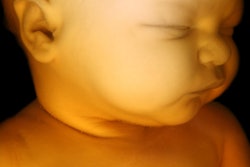

Examining these 3D reconstructions, the researchers found that all seven of the infants experienced considerable fetal head molding with slight differences in terms of which skull bones overlapped the most. Yet only two of the infants maintained a cone-shaped, or "sugarloaf," skull on clinical exam after birth.

Fetal head molding was most prominent on the anterior-posterior axis of the skull, as the group expected, though the largest change in size between pre- and postpartum fetal skull shapes occurred in the fronto-occipital diameter (p = 0.035).

3D finite element reconstruction of the cranial bones before labor and during the second stage of labor. Image courtesy of Dr. Olivier Ami."During vaginal delivery, the fetal brain shape undergoes deformation to varying degrees depending on the degree of overlap of the skull bones," Ami said in a statement. "Fetal skull molding is no more visible in most newborns after birth. Some skulls accept the deformation (compliance) and allow [for] an easy delivery, while others do not deform easily (noncompliance)."

Despite normal pregnancies, two of the patients had to undergo a C-section because the heads of the fetuses turned out to be too large for vaginal delivery. These fetuses were among the three with the greatest degree of fetal head molding. For one of these cases, conventional MRI revealed that the fetal head was not ideally positioned for vaginal delivery even though a clinical exam suggested that the head was in the appropriate location.

Collectively, the 3D MR images showed that the fetal head may undergo significant deformation as it crosses the birth canal, which could negatively affect a child's condition at birth, according to Ami and colleagues.